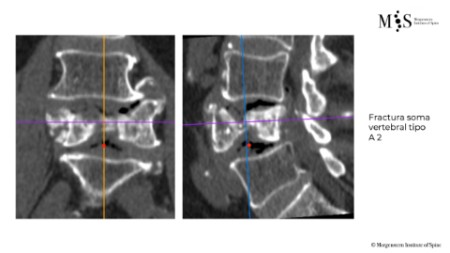

Estabilización percutánea de fracturas vertebrales inestables

En casos de fracturas vertebrales complejas, inestables, conminutas, etc. se requiere una estabilización adicional de la fractura mediante una artrodesis percutánea, y en algunos casos en los que hay compromiso neurológico, una descompresión del canal medular. La artrodesis percutánea permite estabilizar la estrctura comprometida de la columna vertebral y descargar la carga del paciente sobre la fractura. Adicionalmente se suelen cementar las vertebras artrodesas y la fractura vertebral mediante cifoplastia.

Caso clínico con estabilización percutánea de fractura vertebral inestable.